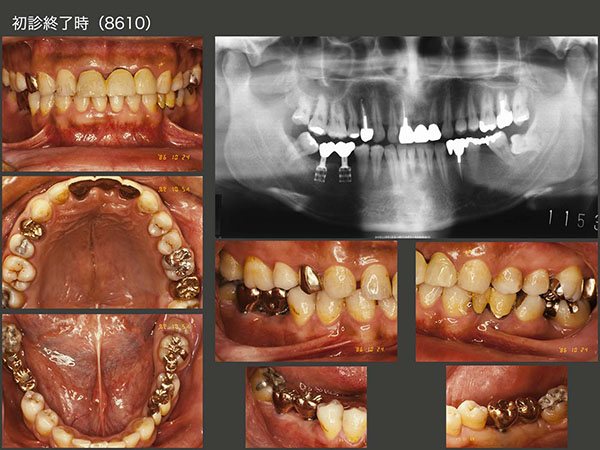

1.インプラント長期経過例

1986年1月初診,31歳男性.当時私は,東京歯科大学病院に勤務しており,その時に担当した患者さん.主訴は右下67の欠損補綴を希望.大学には83年,日本で初めてブローネマルク・インプラントが導入された.歯科医師になって6年目の駆け出しの私としては,ぜひインプラントを用いた治療を行ってみたく,うずうずしていた.丁度同級生にインプラントに詳しい先生がいたので,助手についてもらい,ITIインプラントを植立した.

当時のインプラントはネック部が細く,大きな咬合力には耐えられないと判断し,咬合面をできるだけ小さく製作した.今のインプラントの太さならばもう少し大きく製作できる.しかし小さく製作したことがインプラントに加わる力の軽減に繋がり,インプラントの長期保存に貢献した一つの理由なのかもしれない.

1997年まで,大学病院で定期健診を行っていた.その後暫く拝見することができなかったが,2008年以降,私の診療室まで何時間もかけて通院してくださるようになった.右下のインプラントは30年経過しても順調だが,この理由は2つあると考えている.まず,先にも述べたが咬合面の面積を小さく製作したことが挙げられる.つぎに,インプラントでは嚙んだ時の食感が少ないことから,上下顎に歯のある左側で主に咀嚼していたからと考えている.しかし患者さんは,右側でも咬んでいるとおっしゃっているし,左側の歯に特に問題が生じていないことから,確かに両側で咬んでいるのかもしれない.